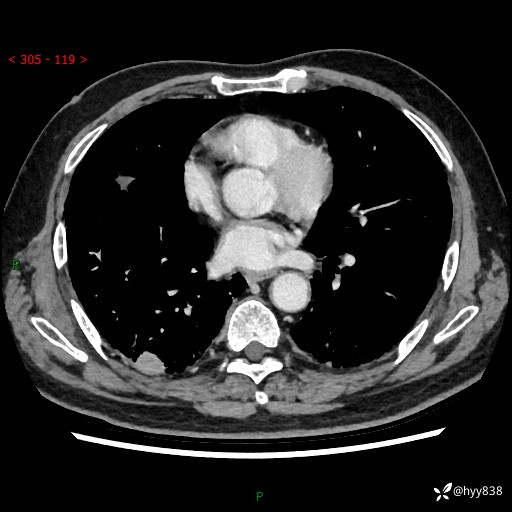

71岁/男,咳嗽伴气促半月。一年前肺手术史,又见两个结节,穿刺结果意外---结果公布~

【现病史】:患者半月前无明显诱因出现咳嗽、咳痰,为白色粘痰,无明显加重与缓解因素,伴气促,无发热,无大量脓痰,无胸痛、咯血,无哮鸣音,到我院就诊,胸部CT示右肺结节增大,并口服药物治疗无明显好转,具体用药不详,为求进一步治疗随来我院,经门诊以“孤立性肺结节”收入我科。 病程中患者精神、饮食可,睡眠不佳,大小便正常,体力下降,体重未见明显下降。

[既往史]:2022-06于当地第一人民医院确诊慢阻肺,现规律使用杰润(1次/日);2023-04-06于当地市第一人民医院行胸腔镜右肺上叶楔形切除术+右肺上叶切除术+淋巴结清扫术+胸膜黏连松解术,确诊为右肺鳞癌 pT2aN0M0 Ib期

【检查】:胸部CT平扫+增强